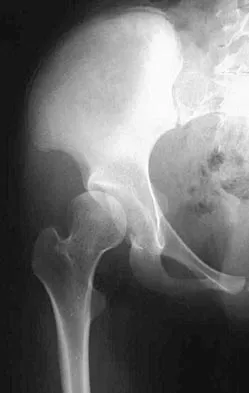

Figures 39a and 39b show the radiographs of an otherwise healthy 10-year-old boy who has had thigh pain and a limp for the past 9 months. Examination reveals that the left lower extremity is 1 cm shorter, with reduced flexion, abduction, and internal rotation on the left side. The patient is at the 50th percentile for height and the 90th percentile for weight. Serum studies will most likely show

Explanation

The patient has a slipped capital femoral epiphysis (SCFE) at a younger than average age (average age 13.5 years for boys and 12.0 years for girls); therefore, an etiology that is not idiopathic must be considered. Hypothyroidism can result in a SCFE, but these children typically fall into the category of less than the 10th percentile for height. SCFE may develop in children with a growth hormone deficiency who have undergone hormonal replacement. Osteodystrophy caused by chronic renal failure may result in a SCFE, but the bone quality is markedly osteopenic on radiographs and the children are chronically ill with both low height and weight percentiles. An elevated estrogen level results in physeal closure and is protective to physeal slippage. Therefore, this child will most likely have normal laboratory values. Loder RT, Hensinger RN: Slipped capital femoral epiphysis associated with renal failure osteodystrophy. J Pediatr Orthop 1997;17:205-211.